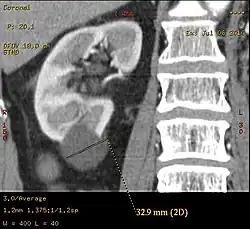

-

Renal ultrasonography of a simple renal cyst with posterior enhancement. -

Bosniak II cyst at the lower pole of right kidney with septations within.